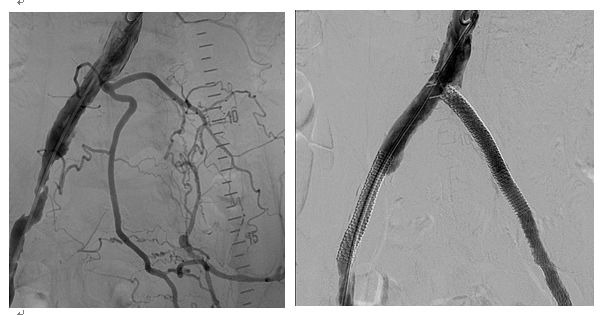

住院后行下肢CTA检查:左髂总动脉、髂外动脉闭塞,右髂外动脉局限性重度狭窄。介入行双髂动脉扩张、支架成形术。如下图。

CTA就是CT血管造影,能够清晰显示全身各部位血管细节,无创而且操作简便,对于血管变异、血管疾病以及显示病变和血管关系有重要价值。

术后患者右足疼痛明显减轻,右足趾溃疡逐渐愈合。